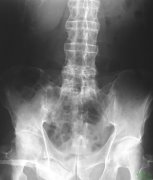

强直性脊柱炎治疗